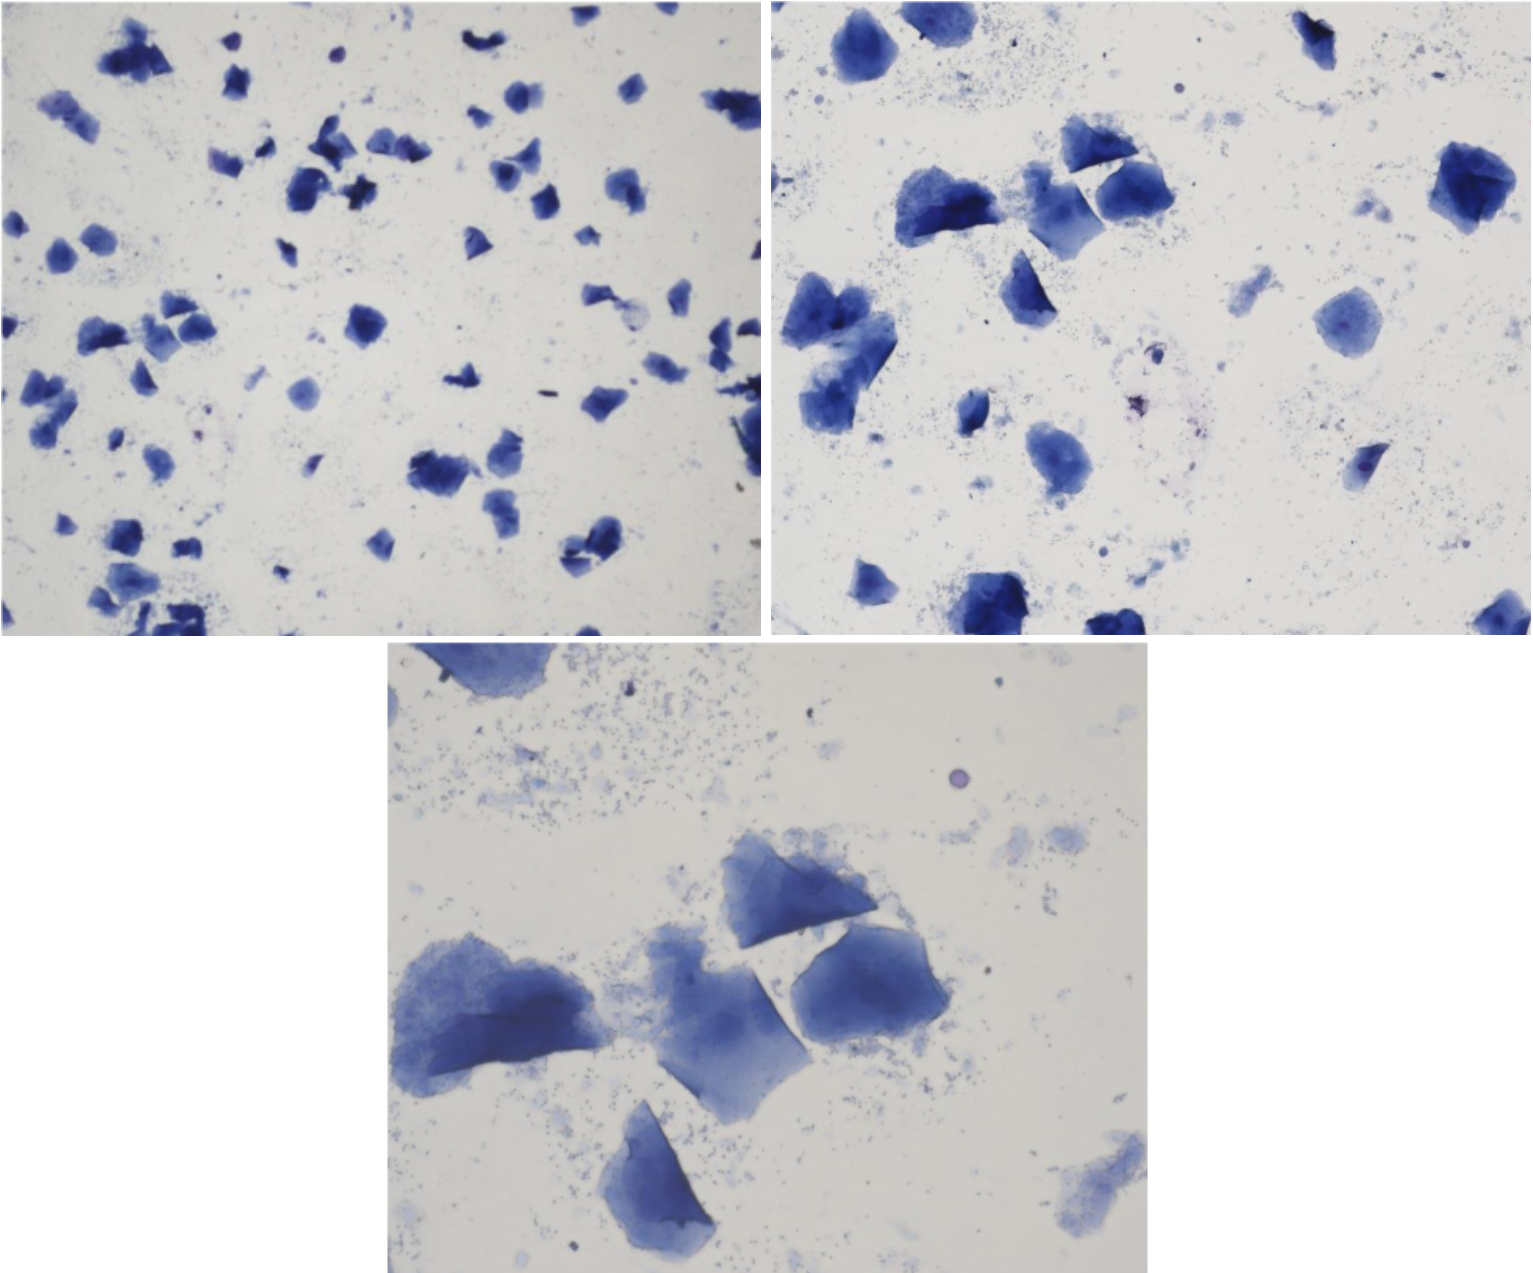

“Cornflakes” utan kärna

Anukleära superficialceller